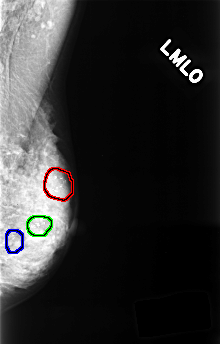

C_0375_1.LEFT_MLO

LEFT_MLO LINES 4464 PIXELS_PER_LINE 2856 BITS_PER_PIXEL 12 RESOLUTION 50 OVERLAY

FILE: C_0375_1.LEFT_MLO.OVERLAY

TOTAL_ABNORMALITIES 3

ABNORMALITY 1

LESION_TYPE CALCIFICATION TYPE PLEOMORPHIC DISTRIBUTION CLUSTERED

ASSESSMENT 4

SUBTLETY 5

PATHOLOGY BENIGN

TOTAL_OUTLINES 1

BOUNDARY

ABNORMALITY 2

ABNORMALITY 3